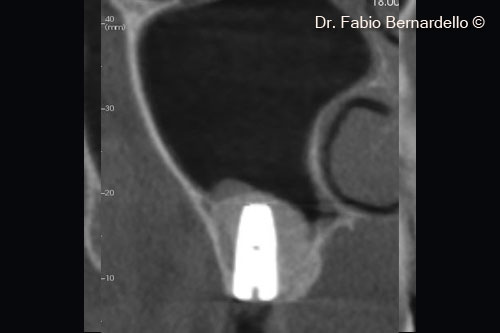

Hình ảnh toàn cảnh xoang hàm trên (Panorex) tại thời điểm ban đầu T0. Gel 40 nâng màng xoang ở vị trí cấy ghép mới và cả phía trên đỉnh của implant cũ ở vị trí số 16

Hình ảnh CBCT mặt cắt ngang tại thời điểm ban đầu (T0). Gel 40 nâng màng xoang tại vị trí cấy ghép mới và cả phía trên đỉnh của implant cũ ở vị trí số 16